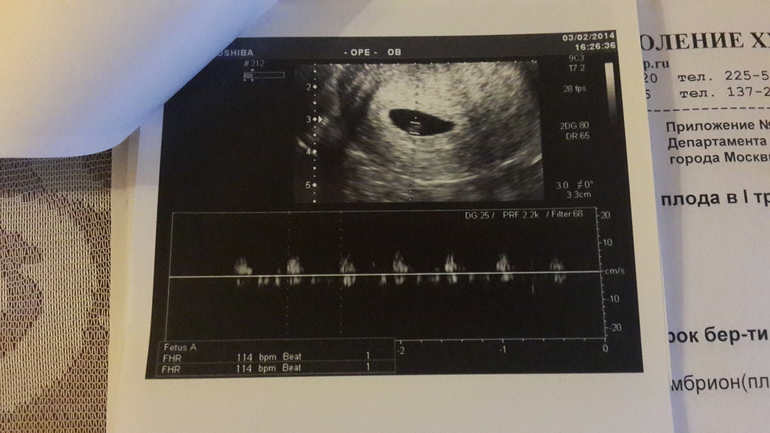

Узи 6 недель нет сердцебиения

Узи 6 недель нет сердцебиения 119 фотографий